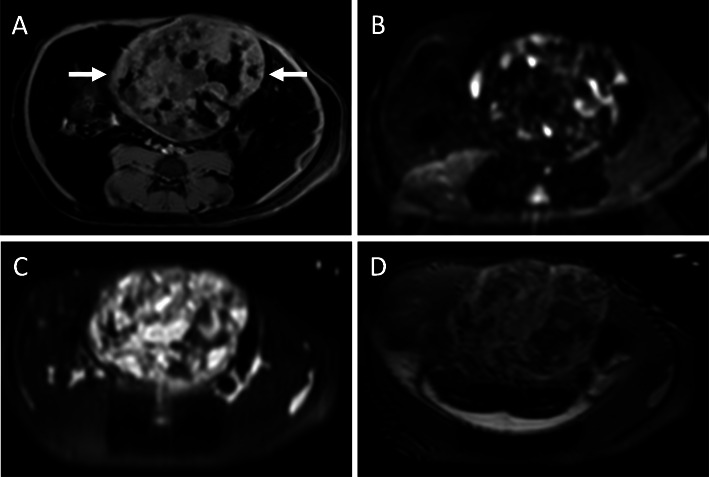

The scout images for the two CT examinations, separated by 5 weeks, showed a large calcified mass that was initially in the left abdomen measured as 5.7 × 3.5 cm (Fig. 1a) and subsequently in the right abdomen measured as 6.5 × 3.8 cm (Fig. 1b). On CT examination, the teratoma measured 6.6 × 4.8 × 4.7 cm and was well-circumscribed, predominantly solid, and heterogenous with soft tissue, fat, and areas of dense calcification (Fig. 1c, d). No fat-fluid levels were identified. Two HCCs were present, one with heterogenous enhancement and necrotic regions. Unlike the enhancement of the HCC after contrast administration, the teratoma did not enhance. The right uterine horn could be traced from the body of the uterus to the mass while the left uterine horn was coiled in the caudal abdomen and pelvis. On ultrasound, the tumor was solid with heterogeneous echogenicity, reflecting the fat content and areas of calcification with acoustic shadowing. Sonolucent areas were present that may have represented cysts. There was little vascularity on color Doppler imaging (Fig. 2). On T1-weighted THRIVE MRI, there was heterogeneously increased signal with areas of signal void representing fat. DWI showed some regions with increased signal. T2-weighted TSE indicated heterogenous hyperintensity while T2-weighted VISTA showed heterogeneous low signal intensity (Fig. 3).

Fig. 3.

Magnetic Resonance Imaging. a THRIVE image of the teratoma (arrows) with heterogeneously increased signal. Signal voids in the teratoma represent fat on this fat-suppressed imaging sequence. b Diffusion-weighted image with focal areas of increased signal. c T2-weighted TSE image with heterogeneous hyperintensity. d T2-weighted VISTA image with heterogeneous low signal intensity